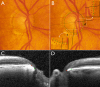

Purpose: We previously demonstrated that most eyes have regionally variable extensions of Bruch's membrane (BM) inside the clinically identified disc margin (DM) that are clinically and photographically invisible. We studied the impact of these findings on DM- and BM opening (BMO)-derived neuroretinal rim parameters.

Methods: Disc stereo-photography and spectral domain optical coherence tomography (SD-OCT, 24 radial B-scans centered on the optic nerve head) were performed on 30 glaucoma patients and 10 age-matched controls. Photographs were colocalized to SD-OCT data such that the DM and BMO could be visualized in each B-scan. Three parameters were computed: (1) DM-horizontal rim width (HRW), the distance between the DM and internal limiting membrane (ILM) along the DM reference plane; (2) BMO-HRW, the distance between BMO and ILM along the BMO reference plane; and (3) BMO-minimum rim width (MRW), the minimum distance between BMO and ILM. Rank-order correlations of sectors ranked by rim width and spatial concordance measured as angular distances between equivalently ranked sectors were derived.

Results: The average DM position was external to BMO in all quadrants, except inferotemporally. There were significant sectoral differences among all three rim parameters. DM-HRW and BMO-HRW sector ranks were better correlated (median ρ = 0.84) than DM-HRW and BMO-MRW (median ρ = 0.55), or BMO-HRW and BMO-MRW (median ρ = 0.60) ranks. Sectors with the narrowest BMO-MRW were infrequently the same as those with the narrowest DM-HRW or BMO-HRW.

Conclusions: BMO-MRW quantifies the neuroretinal rim from a true anatomical outer border and accounts for its variable trajectory at the point of measurement.